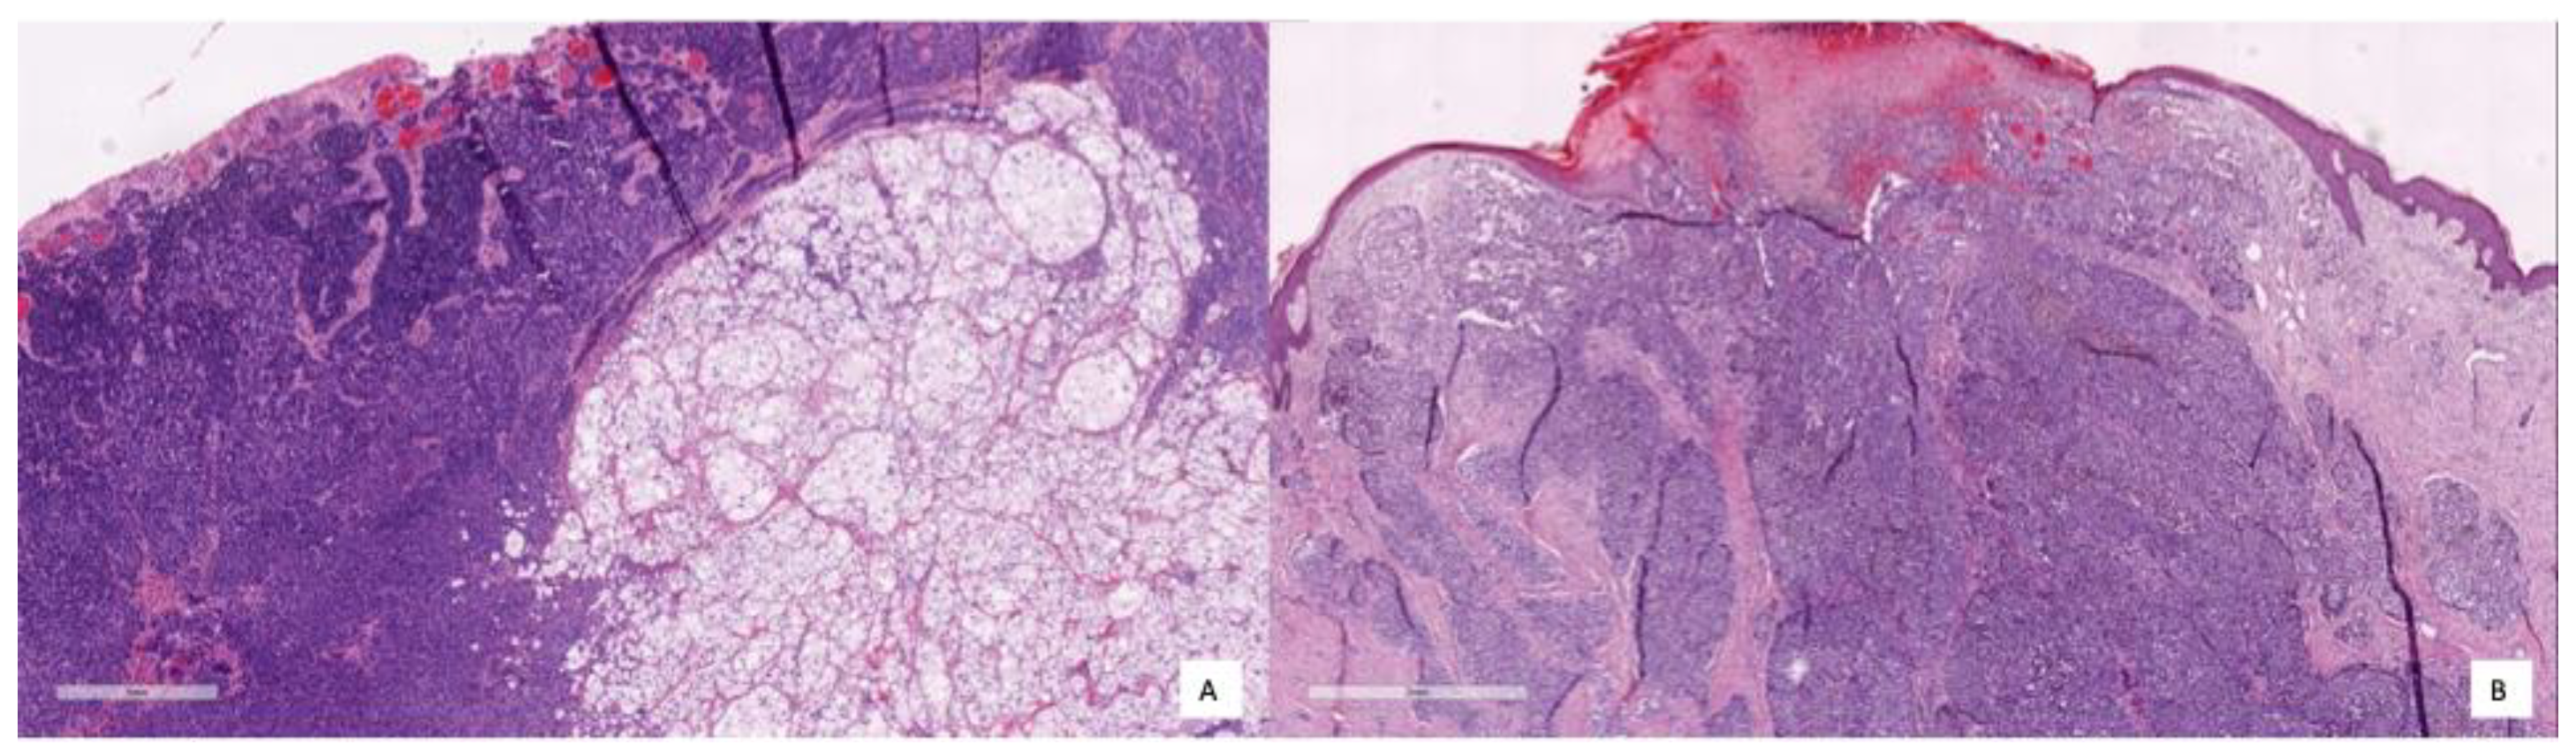

To better illustrate how the model diagnoses, different pictures of the cases corresponding respectively to TNs, TPs and FPs are shown in Figure 8, Figure 9 and Figure 10. Figure 8 shows several examples of TN cases, including a case of dermal melanocytic nevus (Figure 8A), a Reed nevus (Figure 8B), a Spitz nevus (Figure 8C) and a dysplastic nevus (Figure 8D). Figure 9 shows two examples of True Positive (TP) cases, including a spreading superficial melanoma of 3.79mm of Breslow thickness with balloon degeneration (case A) and a superficial spreading melanoma, ulcerated of 5.5 mm of Breslow thickness (case B).

Figure 8.

Representative TN cases illustrating different benign skin lesions: (A) dermal melanocytic nevus, (B) Reed nevus, (C) sclerosing Spitz nevus, and (D) dysplastic nevus. These examples highlight the variability in appearance among non-malignant lesions that may resemble melanoma.

Figure 9.

Representative TN cases: (A) superficial spreading melanoma with balloon degeneration, and (B) ulcerated superficial spreading melanoma. These examples illustrate the morphological diversity of malignant lesions.

Figure 10.

Representative FP cases: (A) deep cellular blue nevus, characterised by dermal proliferation of spindle, fusiform, or ovoid cells with associated melanin pigment (present both within melanocytic tumour cells and macrophages), and stromal sclerosis; (B) lentiginous nevus, exhibiting basal melanocytic proliferation of pigmented melanocytes.